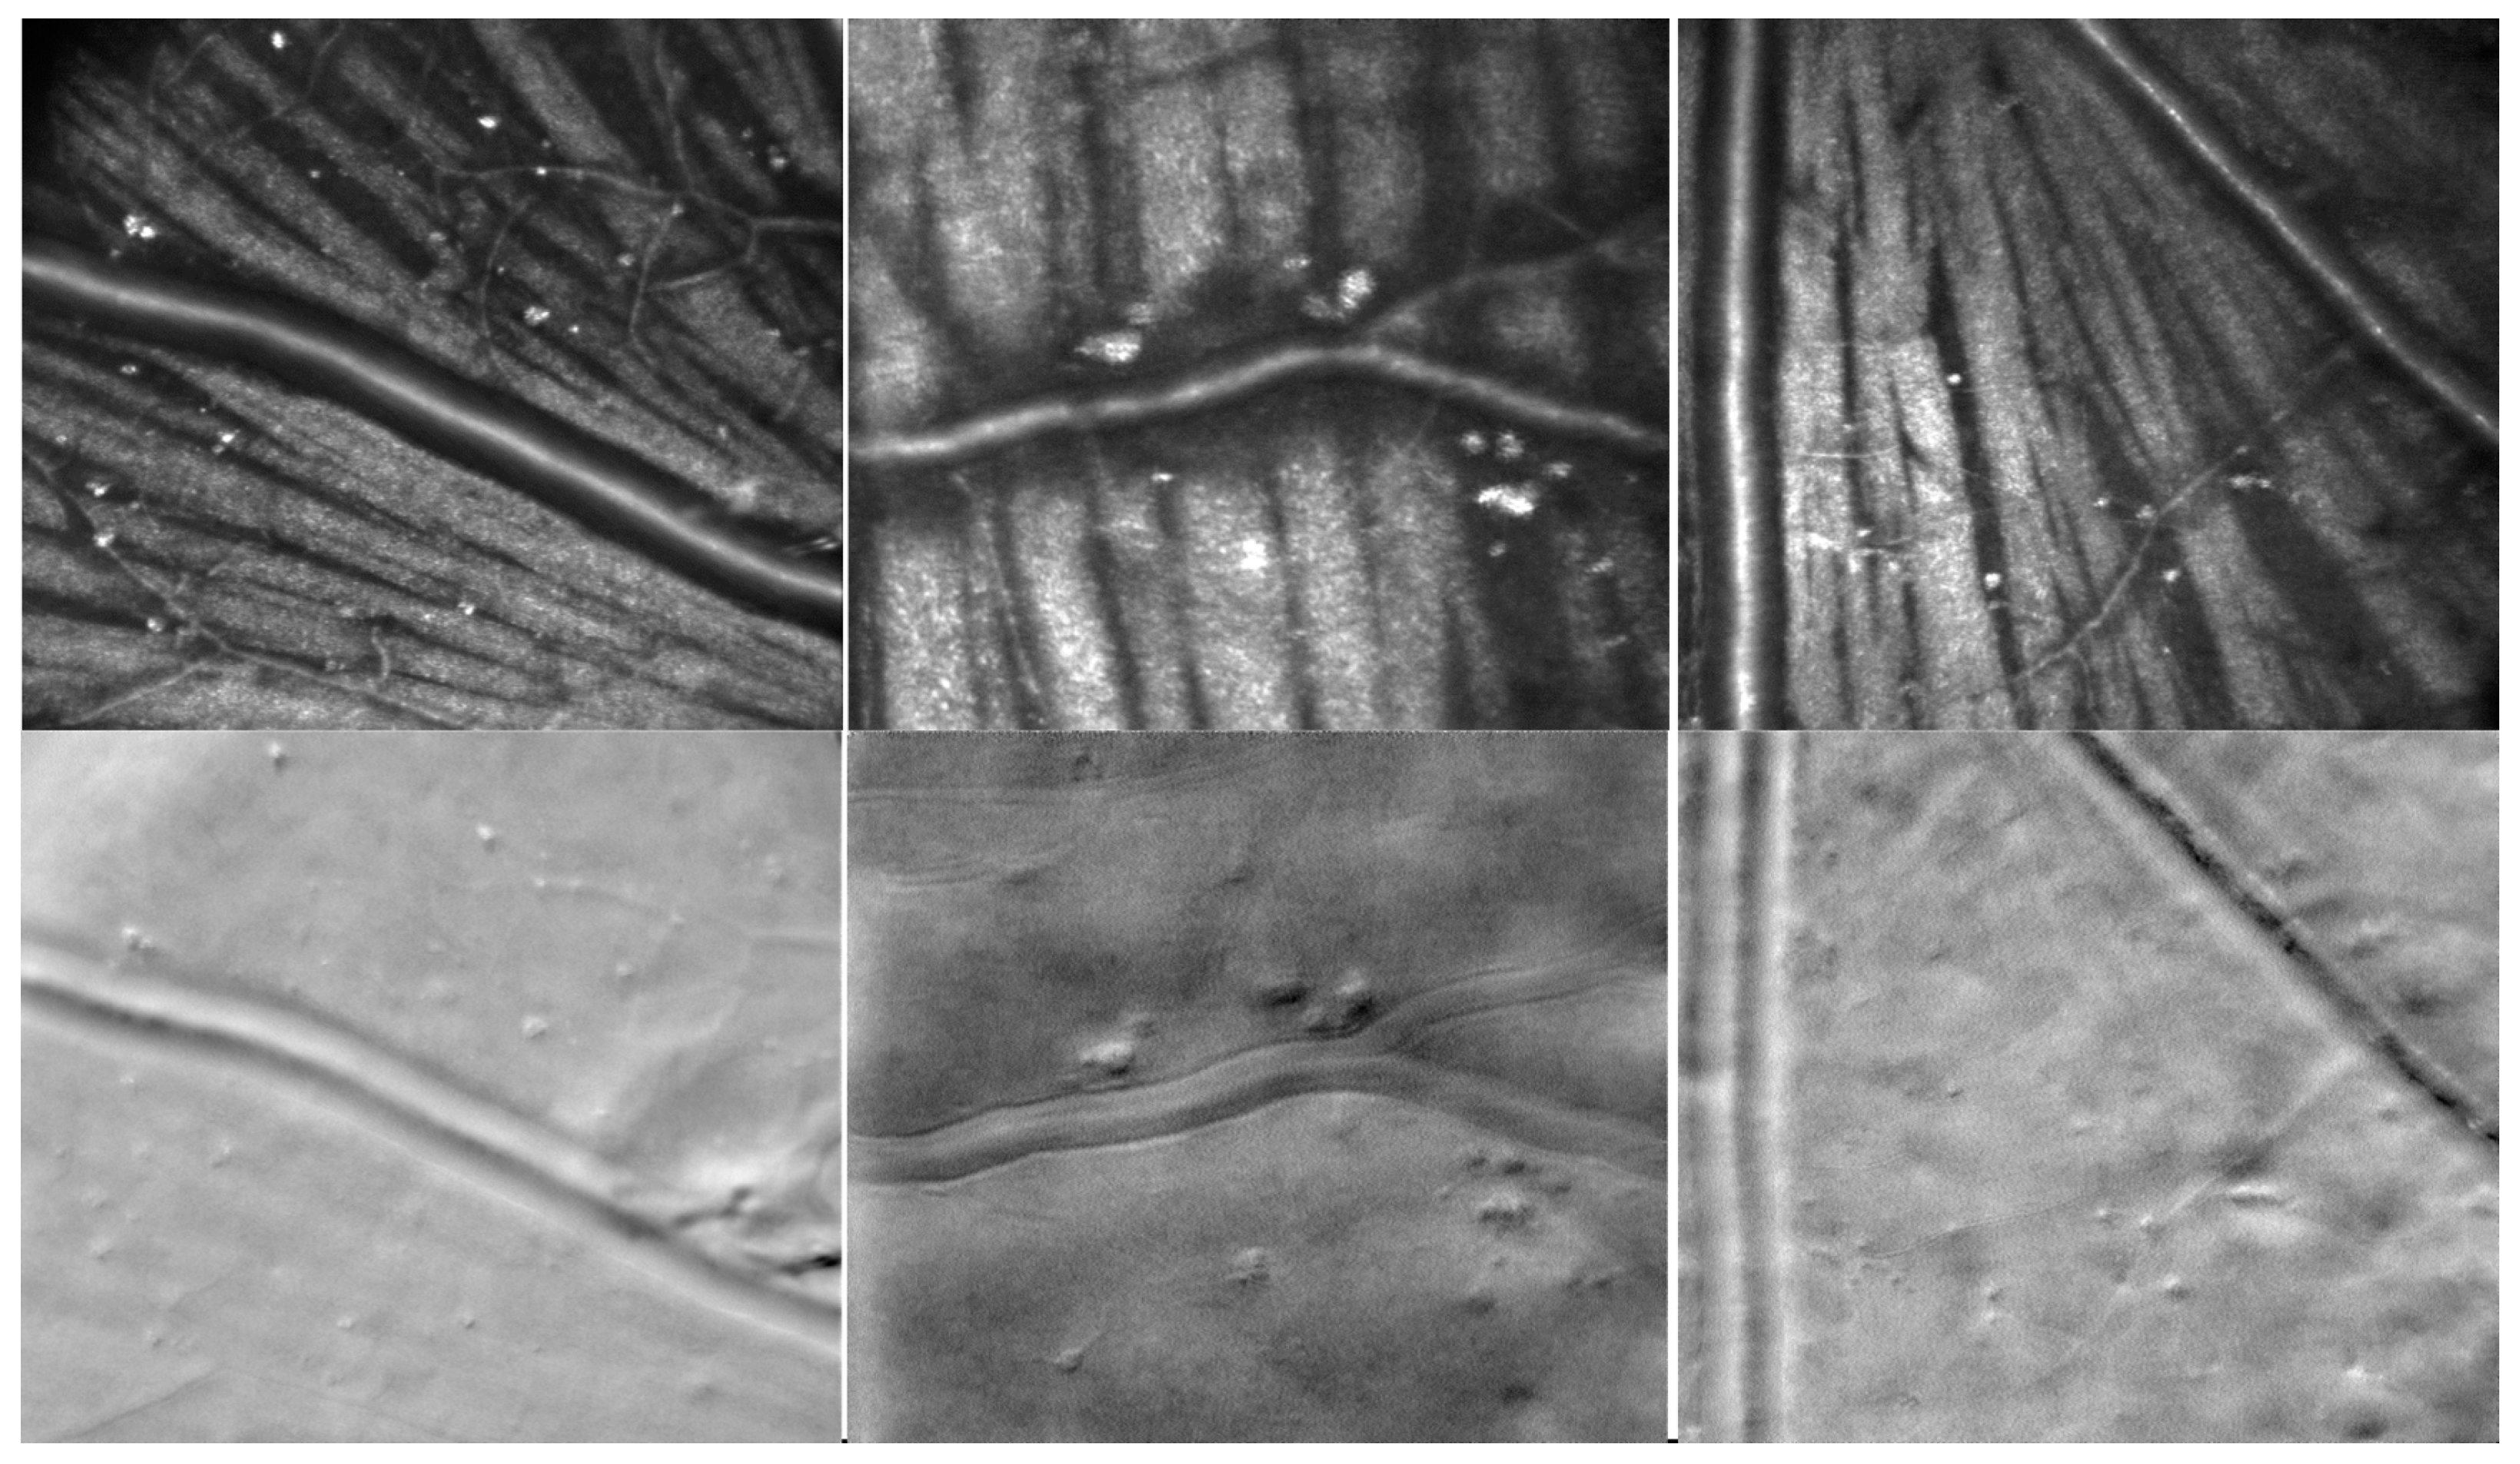

Figure 16 shows examples of the split-detection images (A and D), bright-field confocal images (B and E), and STD image (C). The top line and the center images (A, B, and C) are at the same location, while the bottom line is at the edge of the optic nerve head (ONH).

The second version of CAORI used a TDI camera for offset aperture imaging in addition to the confocal camera. The TDI camera enabled integration over a thick band shifted from the line illumination that was imaged with the confocal line camera. Two bands above and below the line illumination were projected side by side on the TDI camera and were recorded simultaneously, providing two offset aperture images and, therefore, the split-detector image. Figure 16 shows examples of the SPL and confocal AO-LSO images. Panel A shows the detailed structure of a blood vessel wall and the location of several capillaries in the SPL image, while panel B shows the nerve bundles in the confocal image. The STD image in panel C significantly increases the contrast, illustrating the capillaries not visible in the split-detection or the confocal image. As expected, however, vertical edges are not well resolved since the split direction is vertical, perpendicular to the horizontal line illumination. The bottom row of Figure 16 shows in the split-detection image (D) detailed structures at the edge of the ONH not visible in the confocal image (E). The confocal image shows nerve bundles converging into the ONH. The ONH is on the top-right side of these images.

Figure 11. Examples of the SLO, SPL, SD, and STD images. The circles highlight various micro-structures without blood flow that might require additional analysis in an otherwise healthy eye. Image size—2° (~600 µm).

Figure 12. Examples of the SPL, SLO, and STD images. The dotted line indicates the location of the OCT image shown on the right. Image size—2° (~600 µm).